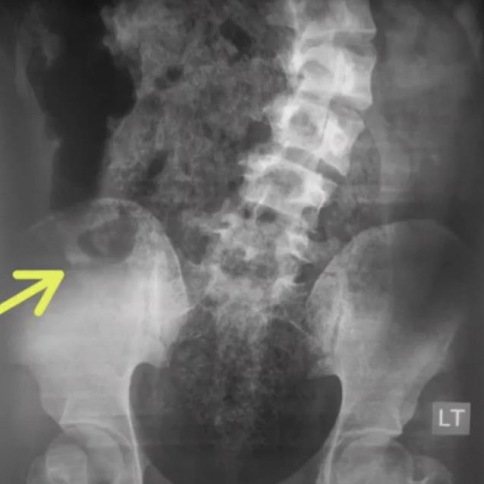

RX

A: Apendicolito

B: Borramiento psoas

C: Asa centinela

D: HiperDensidad de articulación sacroiliaca o FID derecha

E: Curvatura antiálgica